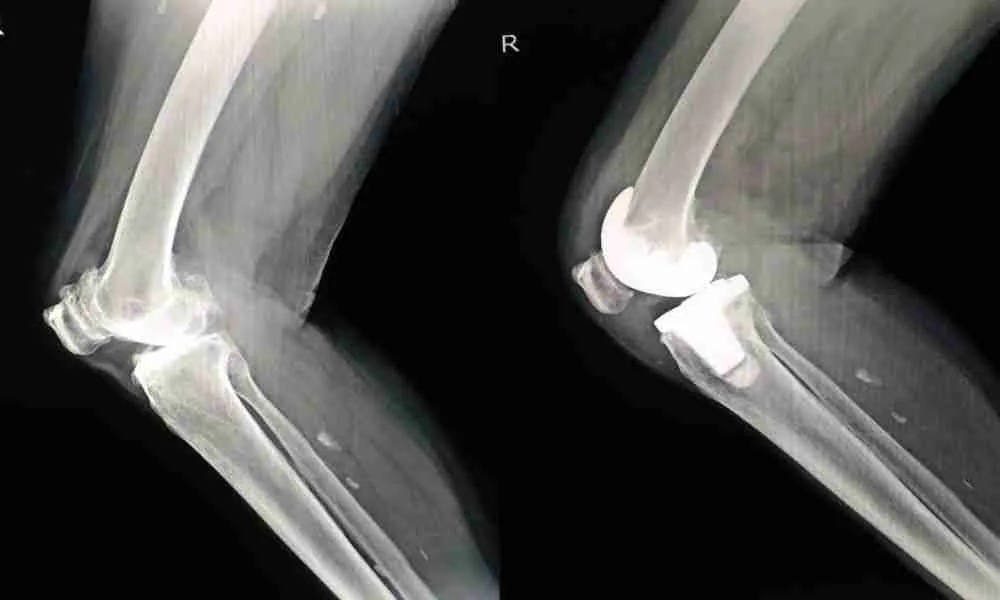

Knee replacement surgery has long been a solution for patients who have severe arthritis or joint degeneration. Traditionally, the procedure has involved using standardized techniques to position the knee implant. However, personalized alignment in knee replacement surgery is gaining prominence as a method that tailors the procedure to an individual’s unique anatomy. This article delves into personalized alignment, its advantages over traditional methods, and how it improves patient outcomes.

Personalized alignment in knee replacement surgery is a patient-specific approach that customizes the placement of the knee implant to suit an individual’s anatomical structure. Instead of relying on a one-size-fits-all technique, this approach considers various factors such as the natural alignment of the leg, ligament balance, and soft tissue constraints, ensuring a more precise fit for the implant. Surgeons use advanced imaging technologies, such as MRI or CT scans, to create 3D models of the patient’s knee, which guide the implant’s placement during surgery. By doing so, personalized alignment aims to restore the knee’s natural movement while reducing stress on surrounding tissues.